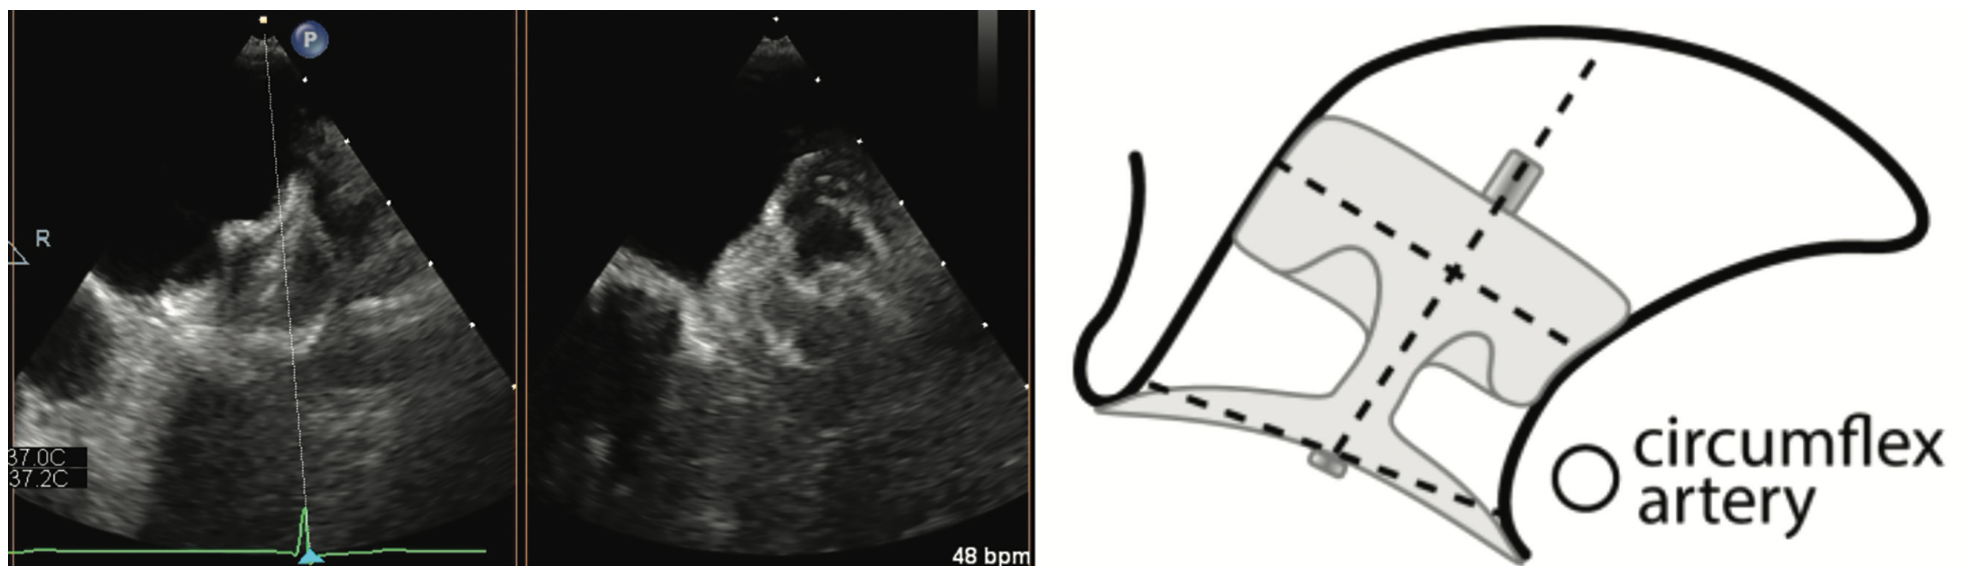

Aside from routine TEE imaging, the preimplantation examination focuses on the LAA dimensions using standardized views derived from the CHAMPION-AF trial.8 In addition to standard views at 0, 45, 90, and 135, each of these views is bisected with a cutting plane. It is also important to document the working depth of the LAA rather than the absolute depth (Figure 1). Measuring both the os and depth of the LAA helps to determine which devices can be offered to the patient. Our institution offers the Amulet, CLAAS System (Conformal Medical), and Watchman FLX device (Table 1). The implanting physician then reviews the images and determines the most appropriate device option.

Using TEE 45 days after implantation, we use the same practices, specific angles for evaluation, and x-plane as in the preimplantation TEE (Figures 2 and 3). We also use a reduced viewing angle to only look at one-half of the device at a time, thus increasing the frame rate. Nyquist limits are reduced to be more sensitive to the lower pressures generated in the LA. The study is read immediately and relayed to the implanting physician. Patients are usually seen in the clinic that afternoon and their anticoagulation regimen is adjusted as needed. Video 1 demonstrates a well-seated Watchman FLX device, and Video 2 shows a well-seated Amulet device.